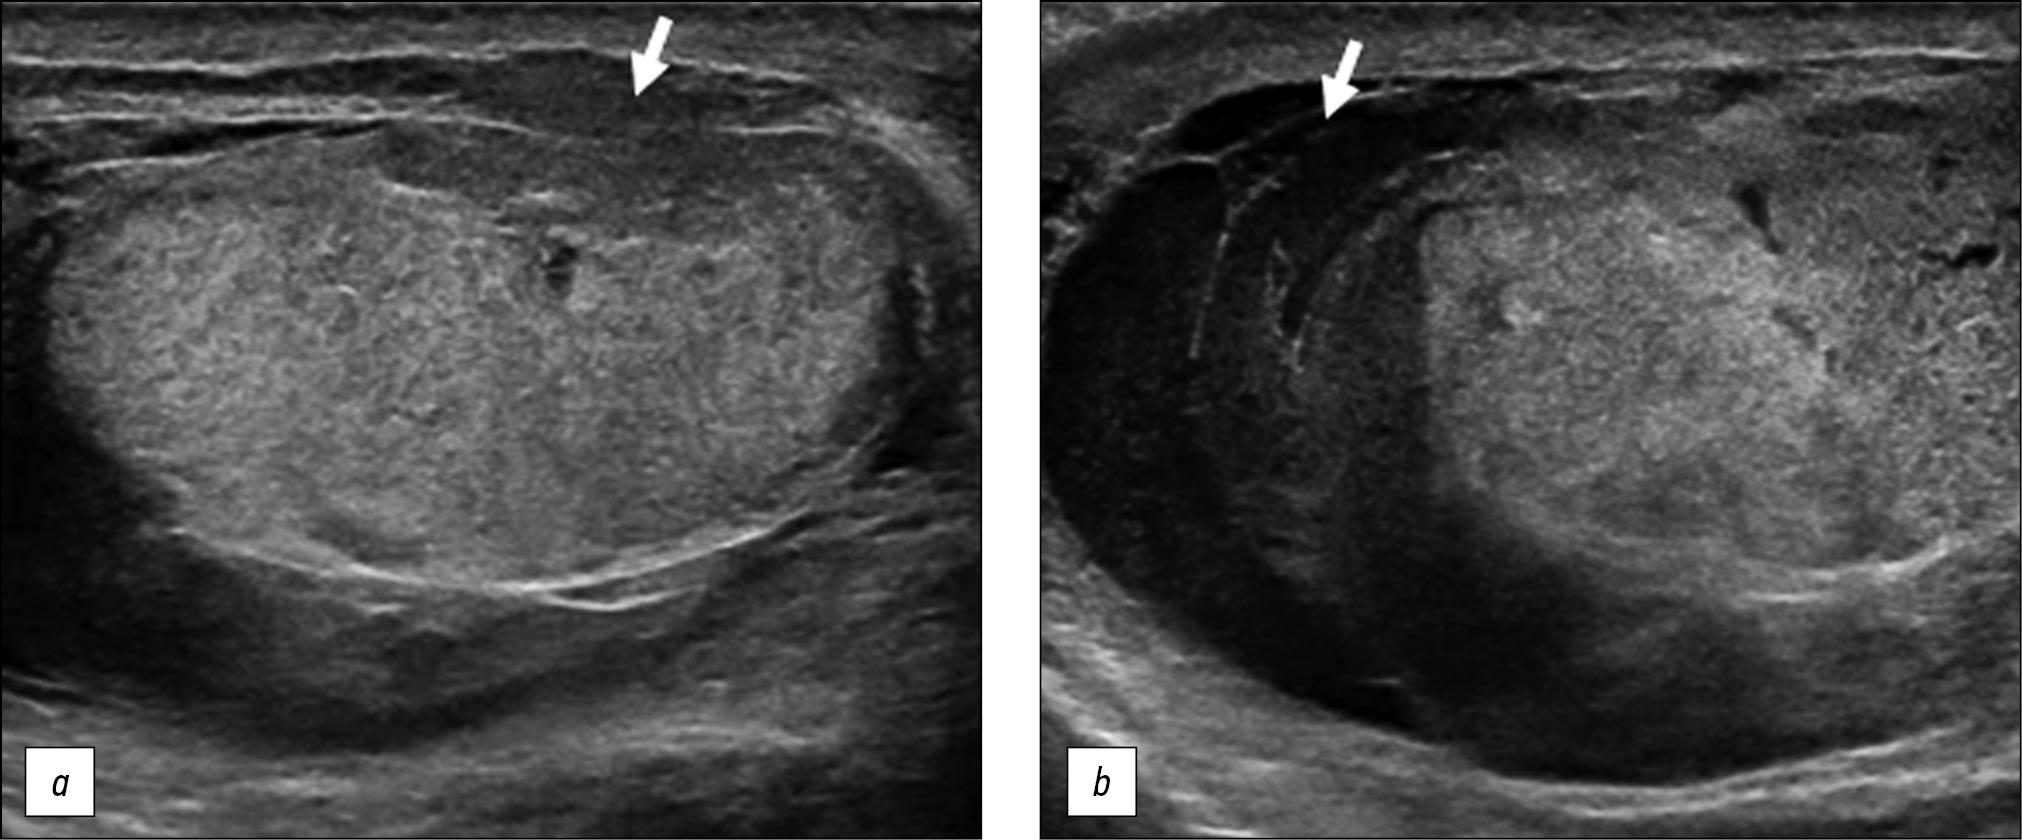

A healthy 15-year-old male teen was hit in the scrotum with a kick in the groin during a football match. He had an immediate and severe pain. After a few hours, although symptoms had improved, he presented to our emergency department with persistent swelling and purplish discoloration of the left scrotum. He did not report any other injuries. The genitourinary examination revealed that the left hemiscrotum was about two times larger than the right with severe ecchymosis. The left testicle was difficult to palpate because of pain and swelling, whereas the right testicle had a normal size and did not reveal any palpable abnormalities. The cremasteric reflex was not elicited on the left side. Scrotal ultrasonography (US) showed moderate scrotal edema and hematocele with a discontinuity in the tunica albuginea characterized by an abnormal contour (Figure 1). Color Doppler US (CDUS) documented a loss of vascularization in the upper pole that extruded into the broken portion of the testicle of approximately 2.5 cm (Figure 2) but no evidence of torsion or infarction. Urology consultation was requested, and a contrast-enhanced US (CEUS) was performed, which confirmed the diagnosis of testicular rupture and determined the amount of the vital parenchyma (Figure 3). The patient was hospitalized for urgent examination of the left hemiscotum based on the US results. During surgery, a large hematocele was evacuated, and a closer inspection of the testicle revealed a lesion of the tunica albuginea. Primary closure of the tunica was performed (Figure 4). The patient made an uneventful recovery, and he was discharged after 4 days.

Figure 4. Intraoperative images. (a) Confirmed rupture of the tunica albuginea. (b) Primary albuginea closure.